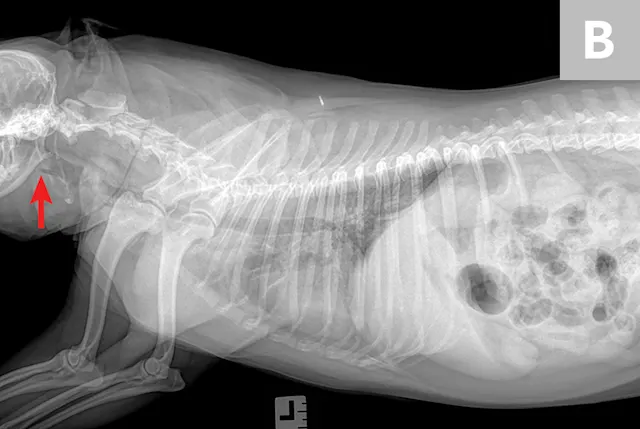

Thoracic radiographs (Figure) show an alveolar lung pattern in the ventral aspect of the right middle lung lobe that is most consistent with aspiration pneumonia or bronchopneumonia. Hemorrhage, neoplasia, and bronchial obstruction are also on the differential list but are considered less likely. Hepatomegaly is present, as is radiographic evidence of possible palate/pharyngeal region swelling and aerophagia.

FIGURE Right lateral (A), left lateral (B), and ventrodorsal (C) thoracic radiographs of the patient. Palate/pharyngeal region swelling can be observed (Barrow), as can an alveolar lung pattern in the ventral aspect of the right middle lung lobe (Carrow), which is most consistent with aspiration pneumonia or bronchopneumonia.